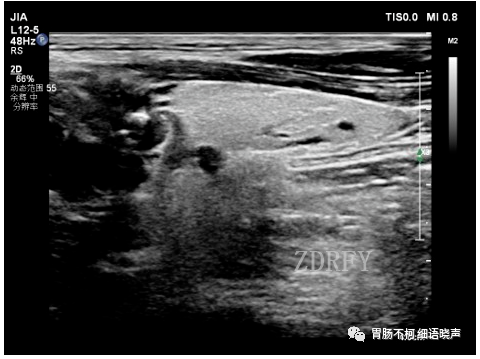

病例一:甲状腺左叶后方低回声型咽食管Killian-Jamieson憩室。

其后方与食管相通。

吞咽口水实验可见团块状强回声涌入。